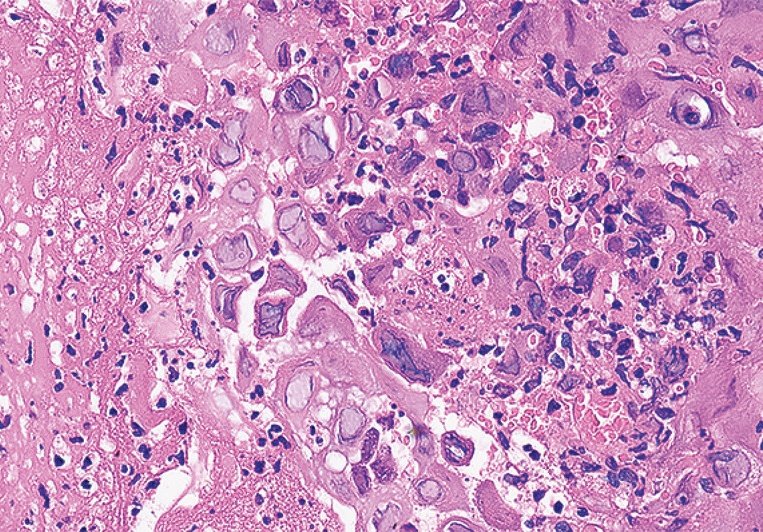

56, female, presents with difficulty swallowing 140 days after allogeneic transplant for AML ๐Ÿ˜ญ GI scopes her, sees ๐Ÿ‘‡๐Ÿฝ Path sees ๐Ÿ‘‡๐Ÿฝ What's going on? Management?